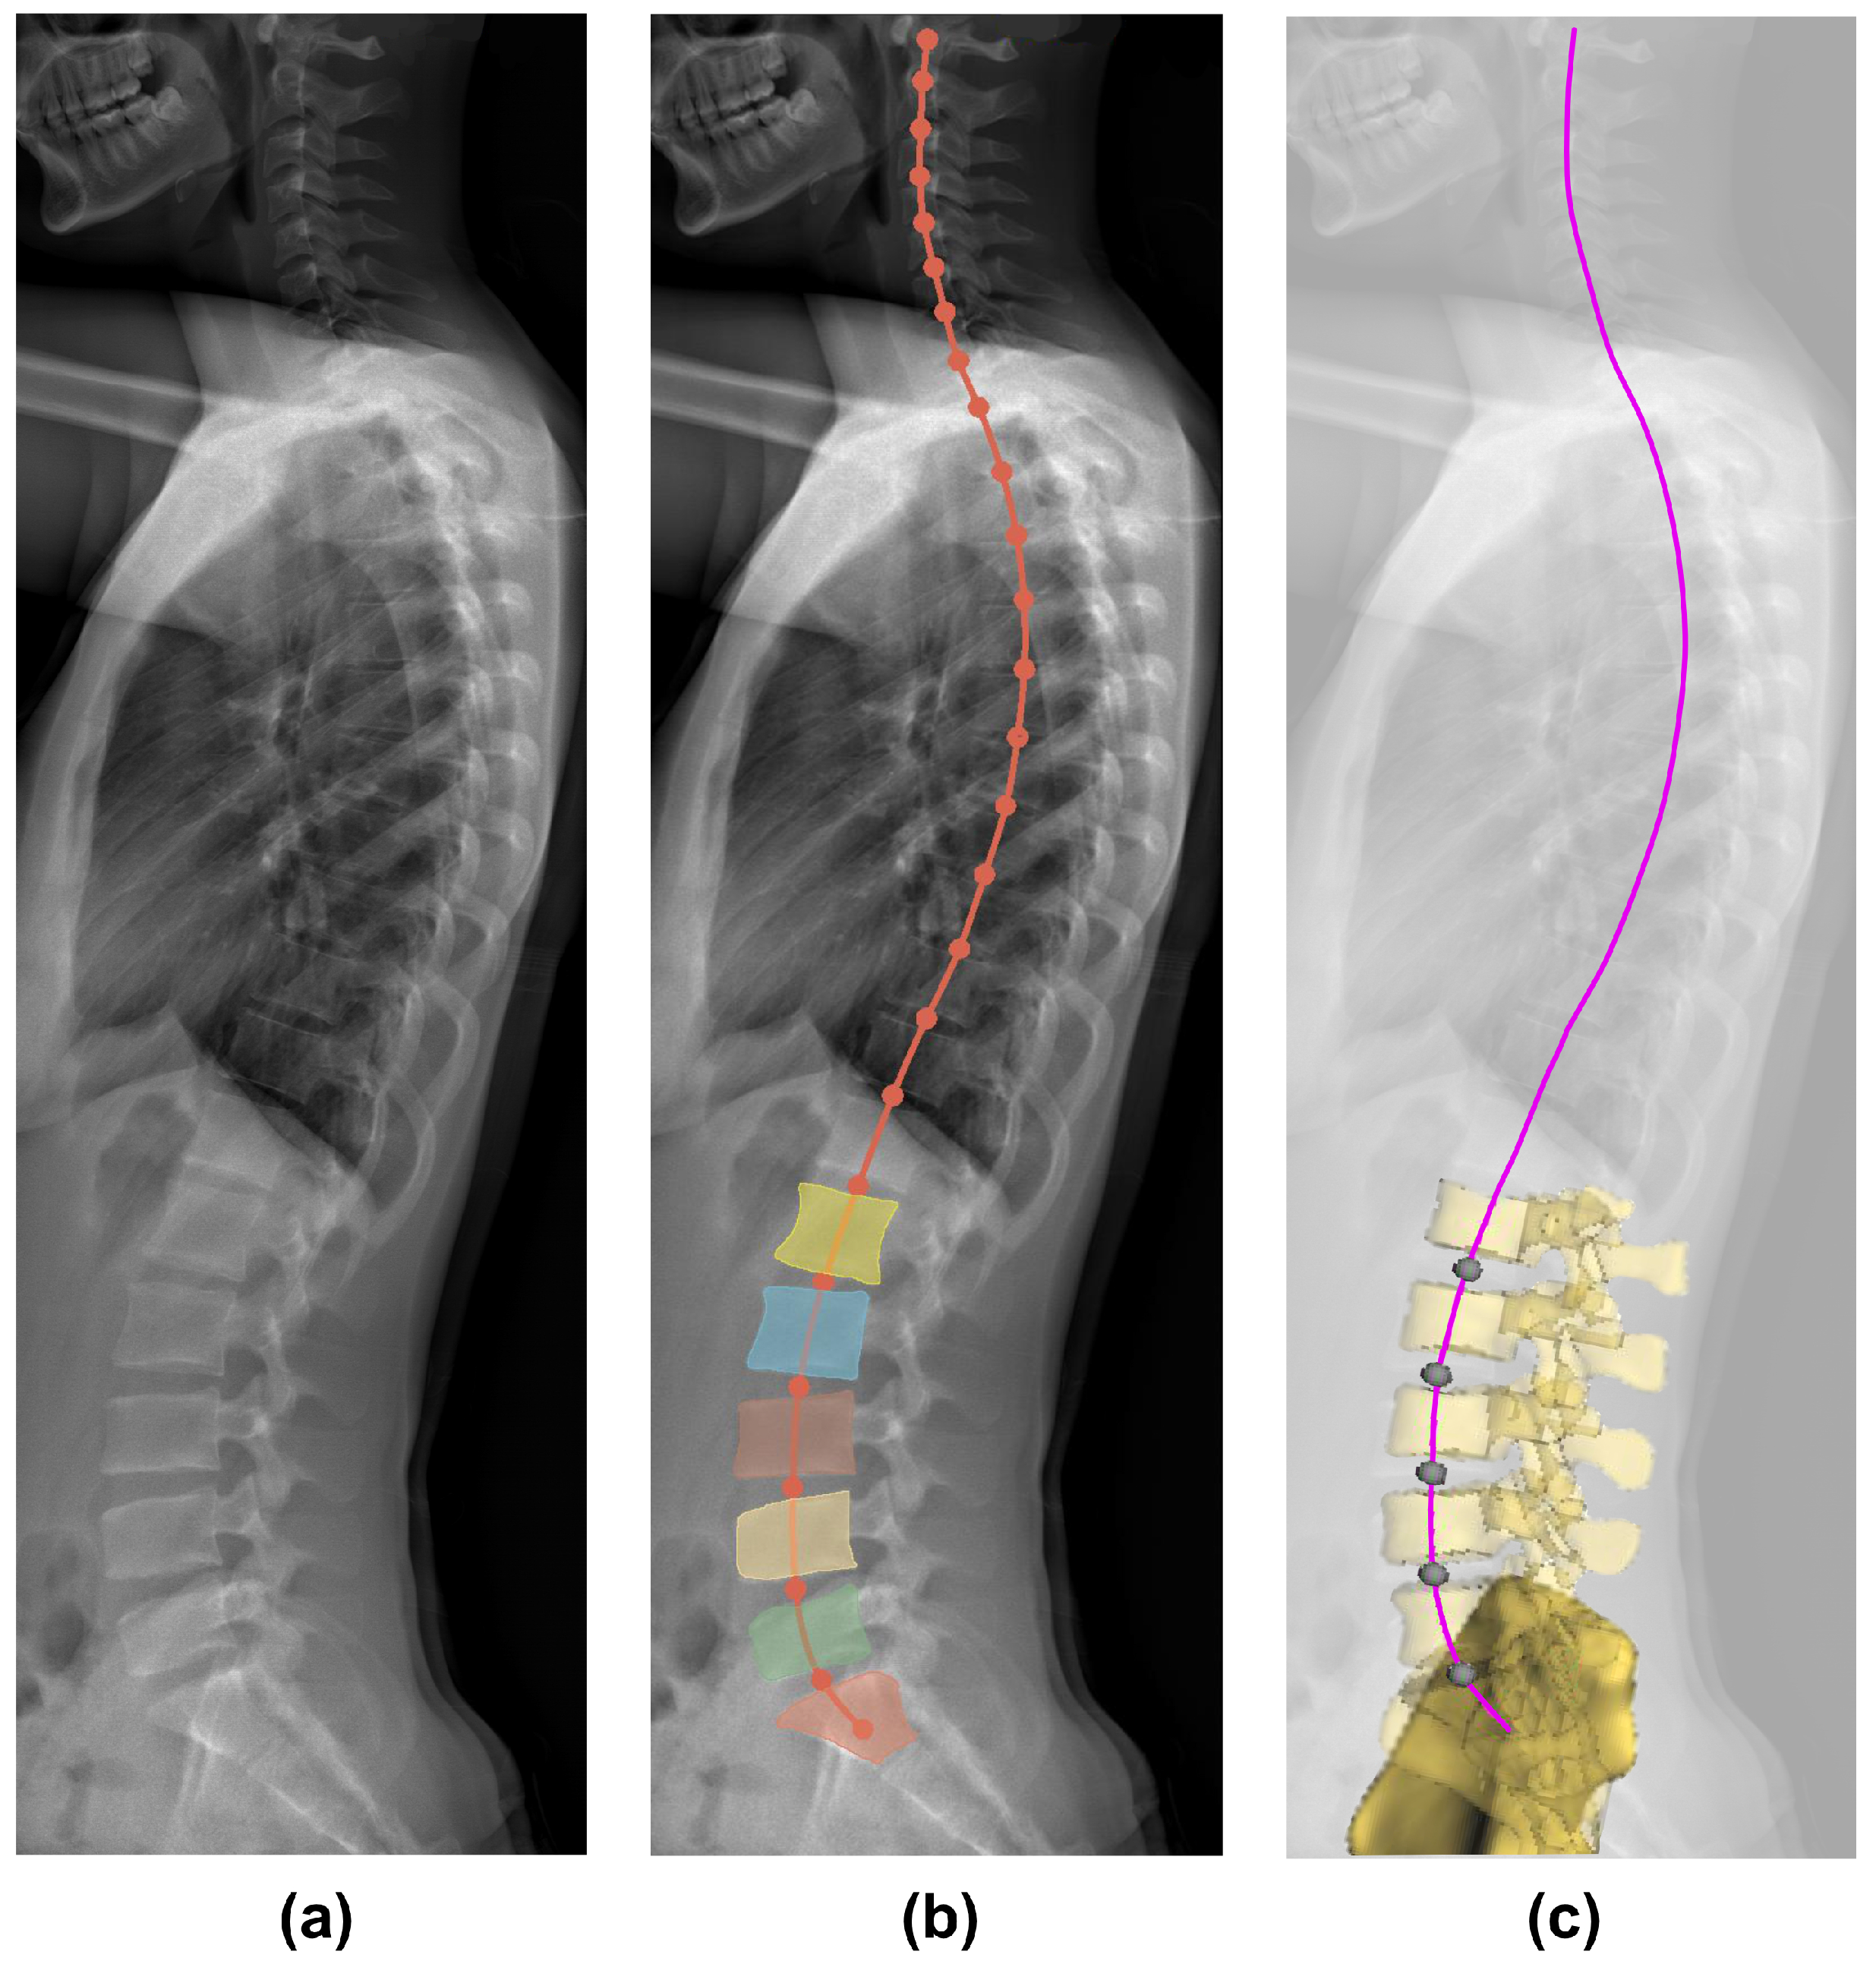

2.1. Lordosis Curve Extraction from Medical Data

3.1. Segmentation of Vertebral Bodies from Medical Data